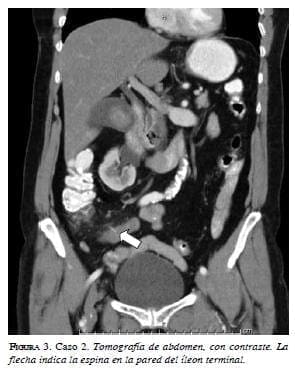

Una mujer de 65 años consultó por dolor abdominal difuso de tipo cólico de cuatro días de evolución, fiebre no cuantificada, sin vómito y hábito intestinal normal. Tenía antecedente de evento cerebrovascular 10 años atrás sin secuelas e histerectomía abdominal por miomatosis. En el examen de ingreso se registró taquicardia, taquipnea, y leucocitosis, y dolor en flanco y fosa ilíaca izquierda. Se practicó TC de abdomen, con contraste, ante la sospecha de enfermedad diverticular complicada, que evidenció perforación del íleon distal por una estructura hiperdensa de 28 mm, asociada con alteración de la grasa adyacente; además, se encontró ureterolitiasis derecha (figuras 2 y 3). Se llevó a cirugía, y se encontró perforación por espina de pescado en el borde antimesentérico, a 15 cm de la válvula ileocecal, con plastrón adyacente a la lesión y sin peritonitis. Se practicó hemicolectomía derecha con anastomosis lateroterminal de íleon a colon transverso con sutura mecánica. En el posoperatorio presentó dehiscencia de la anastomosis, que requirió ileostomía, con fístula mucosa y múltiples lavados abdominales, con una evolución muy tórpida en cuidado intensivo y con deterioro progresivo. Un mes después de su ingreso al hospital, la paciente falleció por falla respiratoria.

La Tomografía computadorizada (TC) se considera el método de imaginología de elección, porque permite identificar la presencia, el sitio y la causa de la perforación intestinal 19-22. Se puede ver extravasación del medio de contraste oral, engrosamiento de la pared intestinal y aire libre en la cavidad abdominal, como signos radiológicos directos que sugieren perforación intestinal 23-25. La infiltración grasa, el absceso o el flegmón adyacente al intestino, y la obstrucción intestinal asociada, son signos indirectos 6.